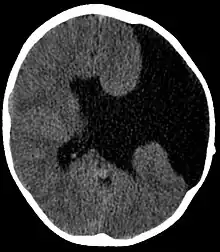

Axial CT scan showing schizencephaly in a 6-year-old child

Schizencephaly (from Greek skhizein 'to split', and enkephalos 'brain')[1][2] is a rare birth defect characterized by abnormal clefts lined with grey matter that form the ependyma of the cerebral ventricles to the pia mater. These clefts can occur bilaterally or unilaterally. Common clinical features of this malformation include epilepsy, motor deficits, and psychomotor retardation.[3]